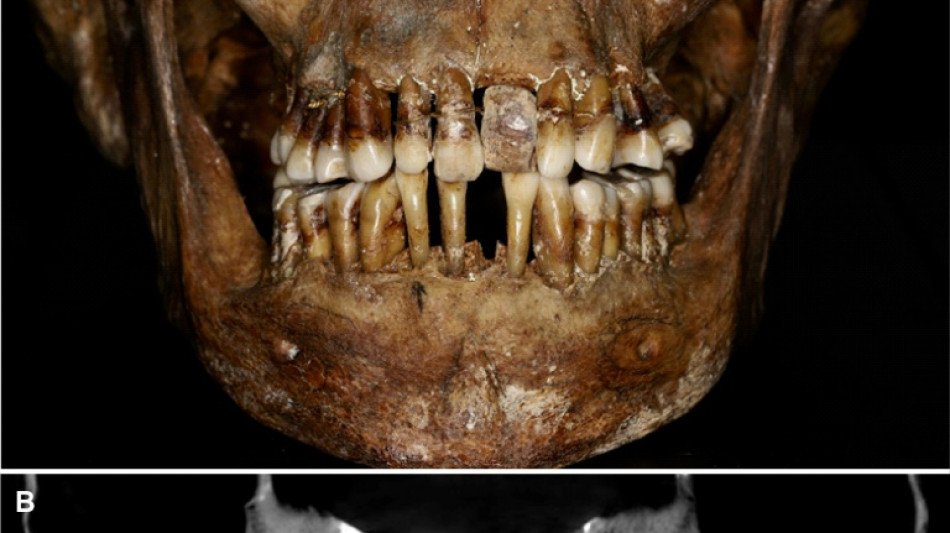

La sépulture d'Anne d'Alègre, morte en 1619 à l'âge de 54 ans, avait été déterrée lors d'une fouille au château de Laval, en 1988. Embaumé dans un cercueil de plomb, le squelette était particulièrement bien conservé, sa dentition aussi.

Plus de trente ans après, une équipe comprenant des archéologues et des dentistes dévoile qu'Anne d'Alègre était atteinte d'une maladie parodontale qui provoque le déchaussement progressif des dents, selon une étude parue cette semaine dans Journal of Archeological Science.

Les images radiologiques par "Cone Beam", un scanner en 3D, montrent que la patiente portait une prothèse dentaire remplaçant une incisive, soutenue par des fils d'or, ainsi qu'une ligature de contention sur des pré-molaires.

Des examens en macroscopie ont déterminé que cette prothèse était en ivoire d'éléphant, écartant la piste de l'ivoire de dents d'hippopotame, également utilisé à l'époque.

A long terme, ce traitement, ainsi que les "multiples resserrages nécessaires, ont entraîné l'instabilité des dents voisines", détaille l'Inrap.